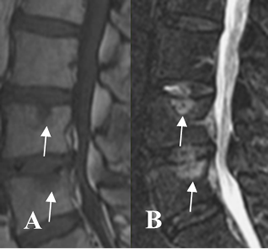

El compromiso inflamatorio del disco intervertebral, es conocido como espondilodisquitis o lesión de Anderson, que es una condición no infecciosa. (21).

Produce alteración en la señal y configuración del disco y las placas terminales, las cuales con hipointensas en T1 e hiperintensas en STIR, adquiriendo una forma semihemisférica. Los cambios comprometen mas la parte central, que los bordes anterior y posterior y son detectados con la RM, antes que la Rx simple. (21, 22). (Fig 59 H a 59 J).

Fig 59 J. Espondilodisquitis.

A y B: RM STIR. Edema trabecular de las placas terminales y rodeando un espacio intervertebral, por espondilodisquitis. En un control 10 meses después de iniciar el tratamiento, han desaparecido los cambios inflamatorios.